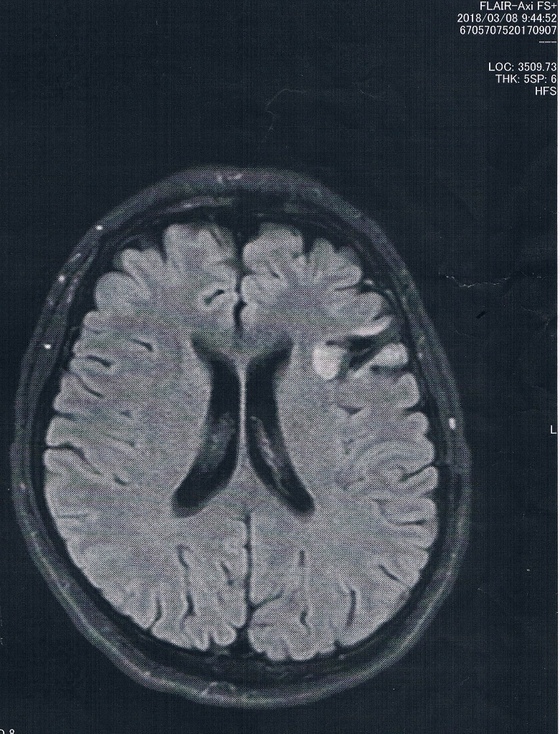

今回2018/3/8(手術後45か月)のMRI画像